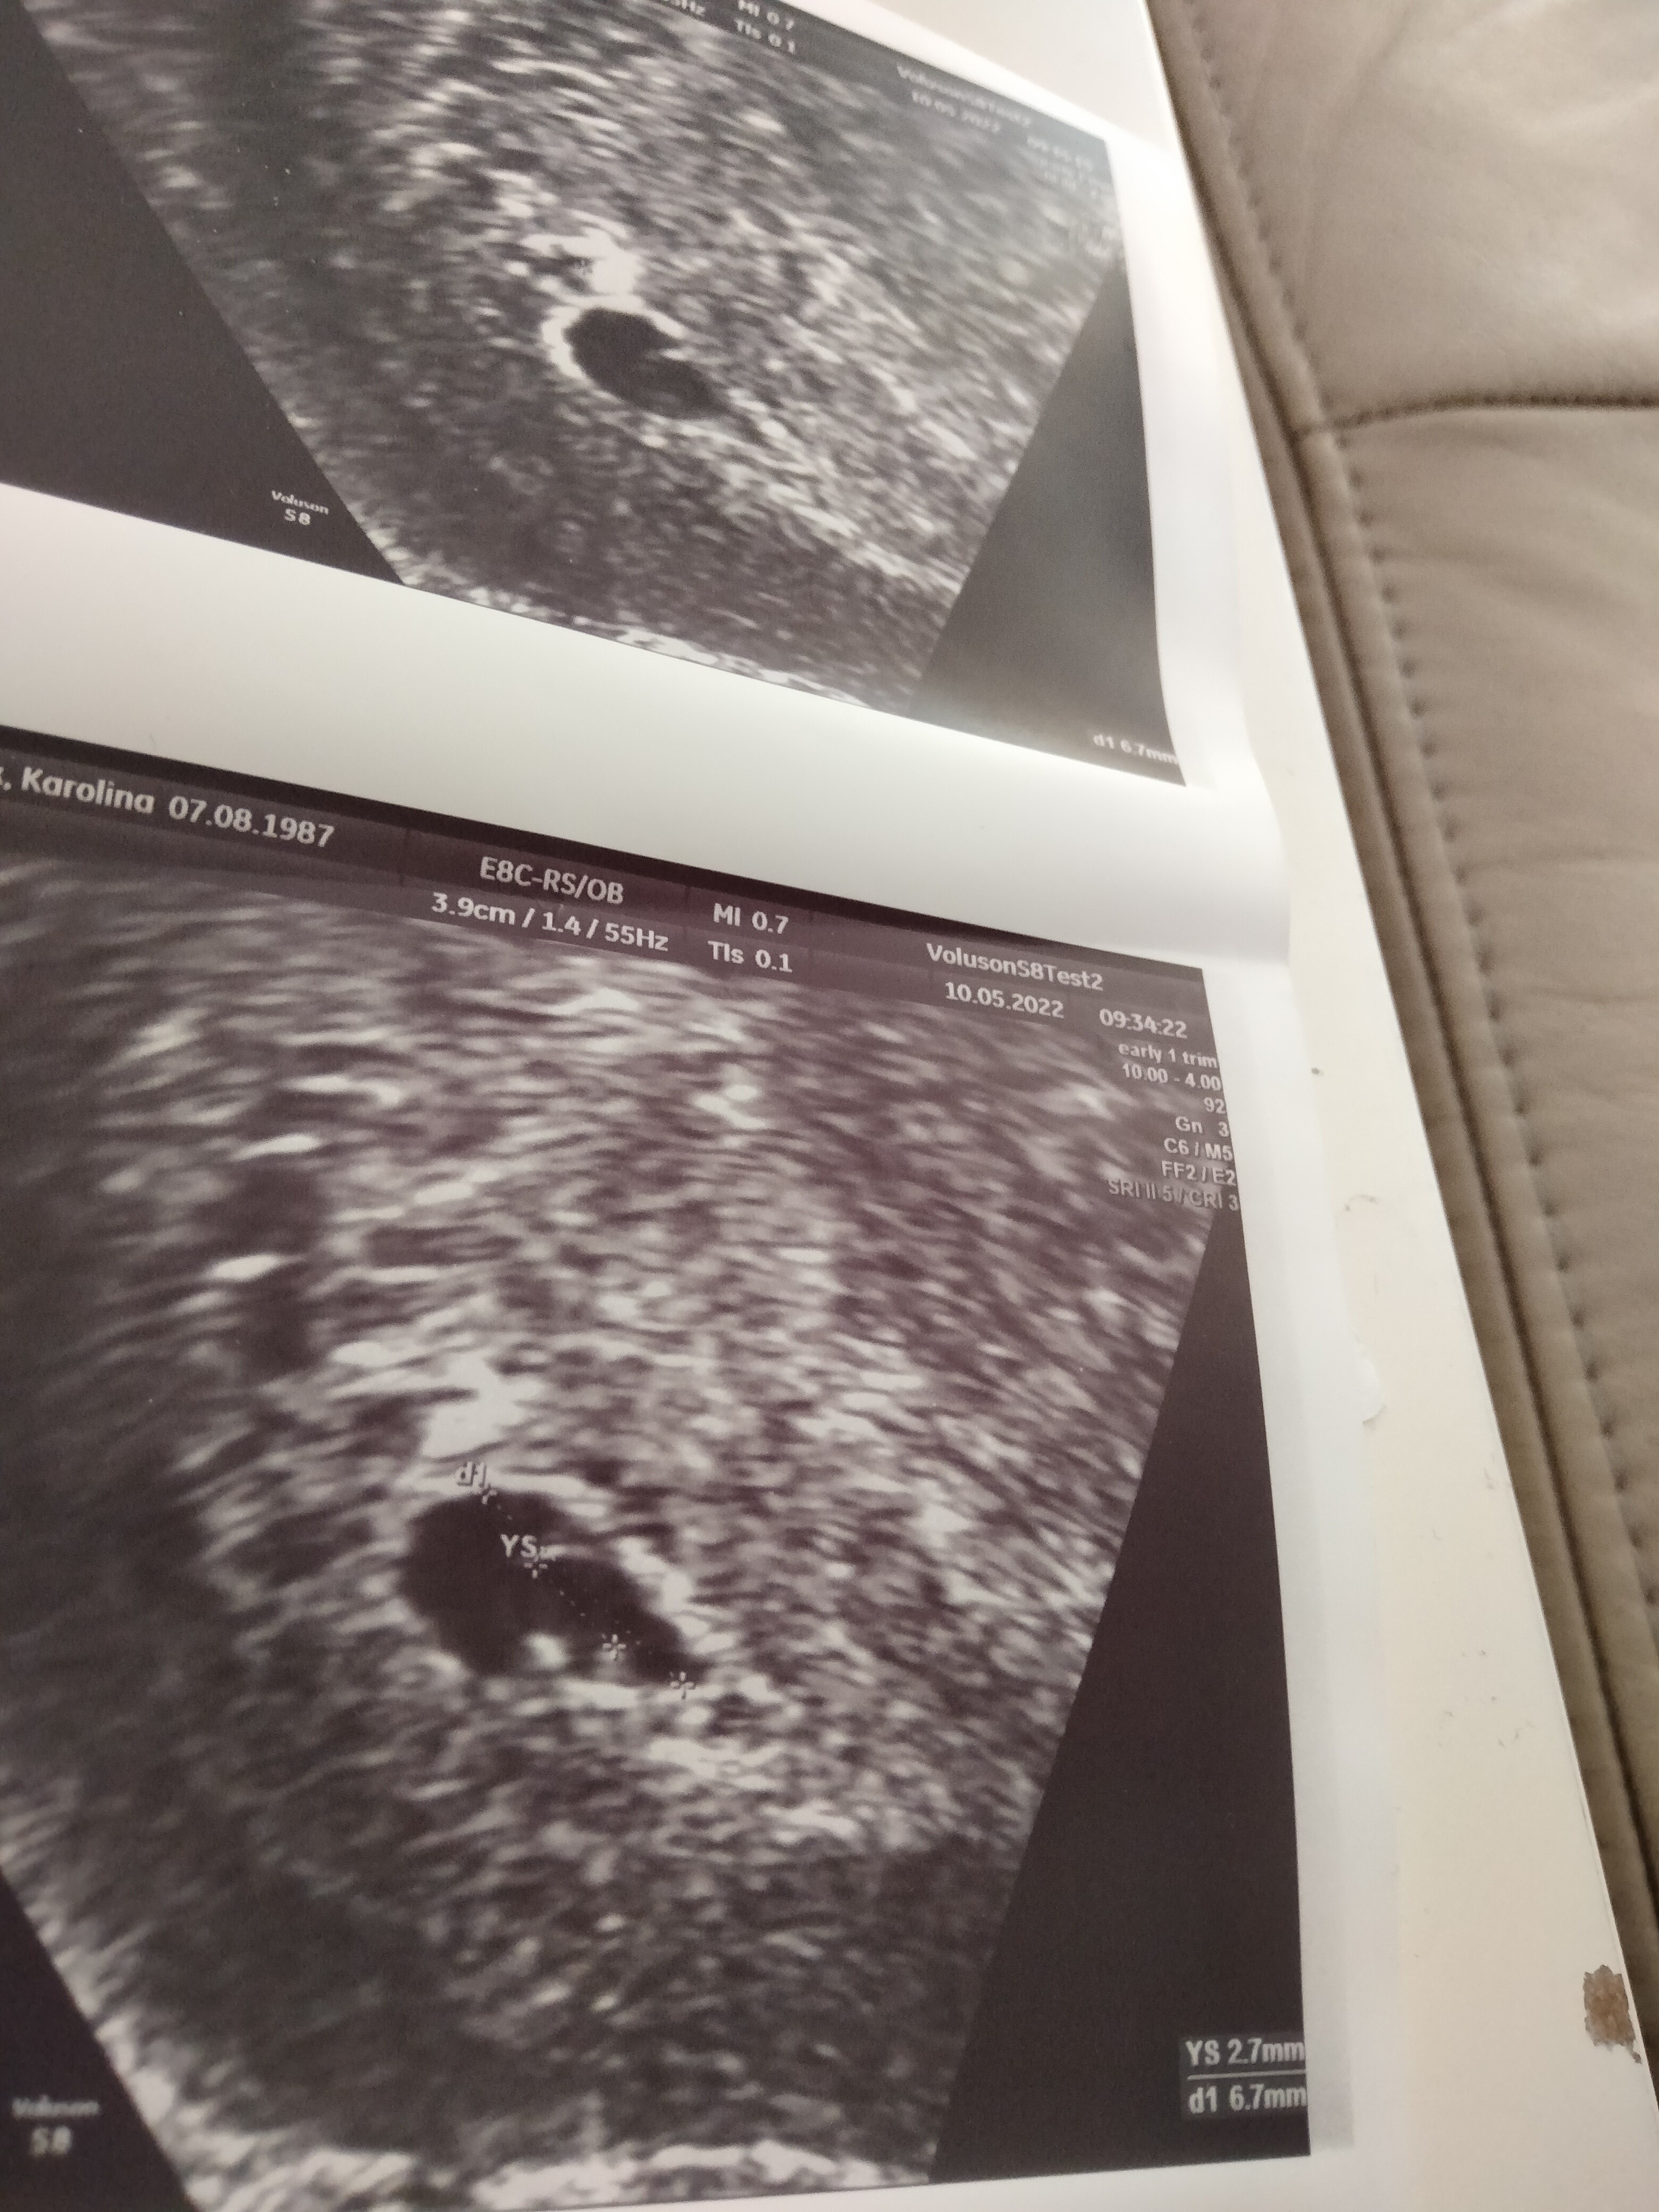

Ale co dokładnie ? Widać pęcherzyk zoltkowy, malutki (to dobrze :)) jak to w młodej ciąży. Na jego brzegu gdzieś się czai zarodek (być może tutaj po prawej dolnej stronie) ale to już trzeba ruszać głowicą by być pewnym.

Jeśli jest YS to JEST zarodek - czasami zbyt mały by było go widać na usg ale jest :) po pojawieniu się YS 1-2 dni później można zobaczyć zarodek a kilka dni później serduszko :)